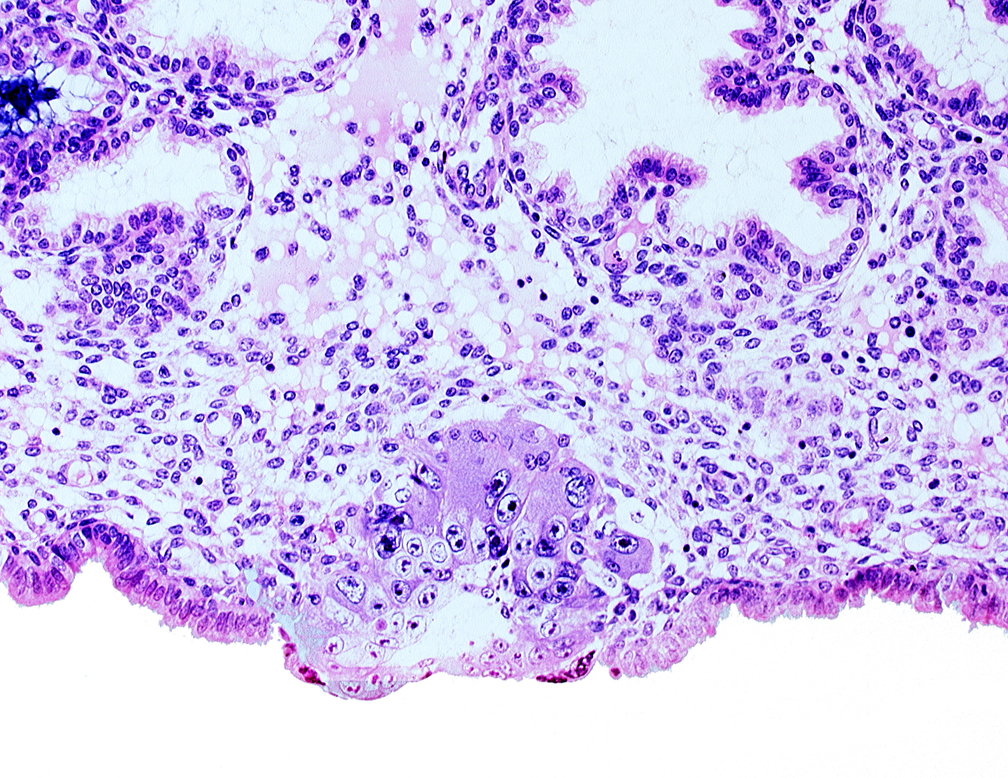

Carnegie Embryo #8155 | Location: 04-03-03

Keywords: blastocystic cavity (blastocoele), cytotrophoblast, extra-embryonic mesoblast, solid syncytiotrophoblast